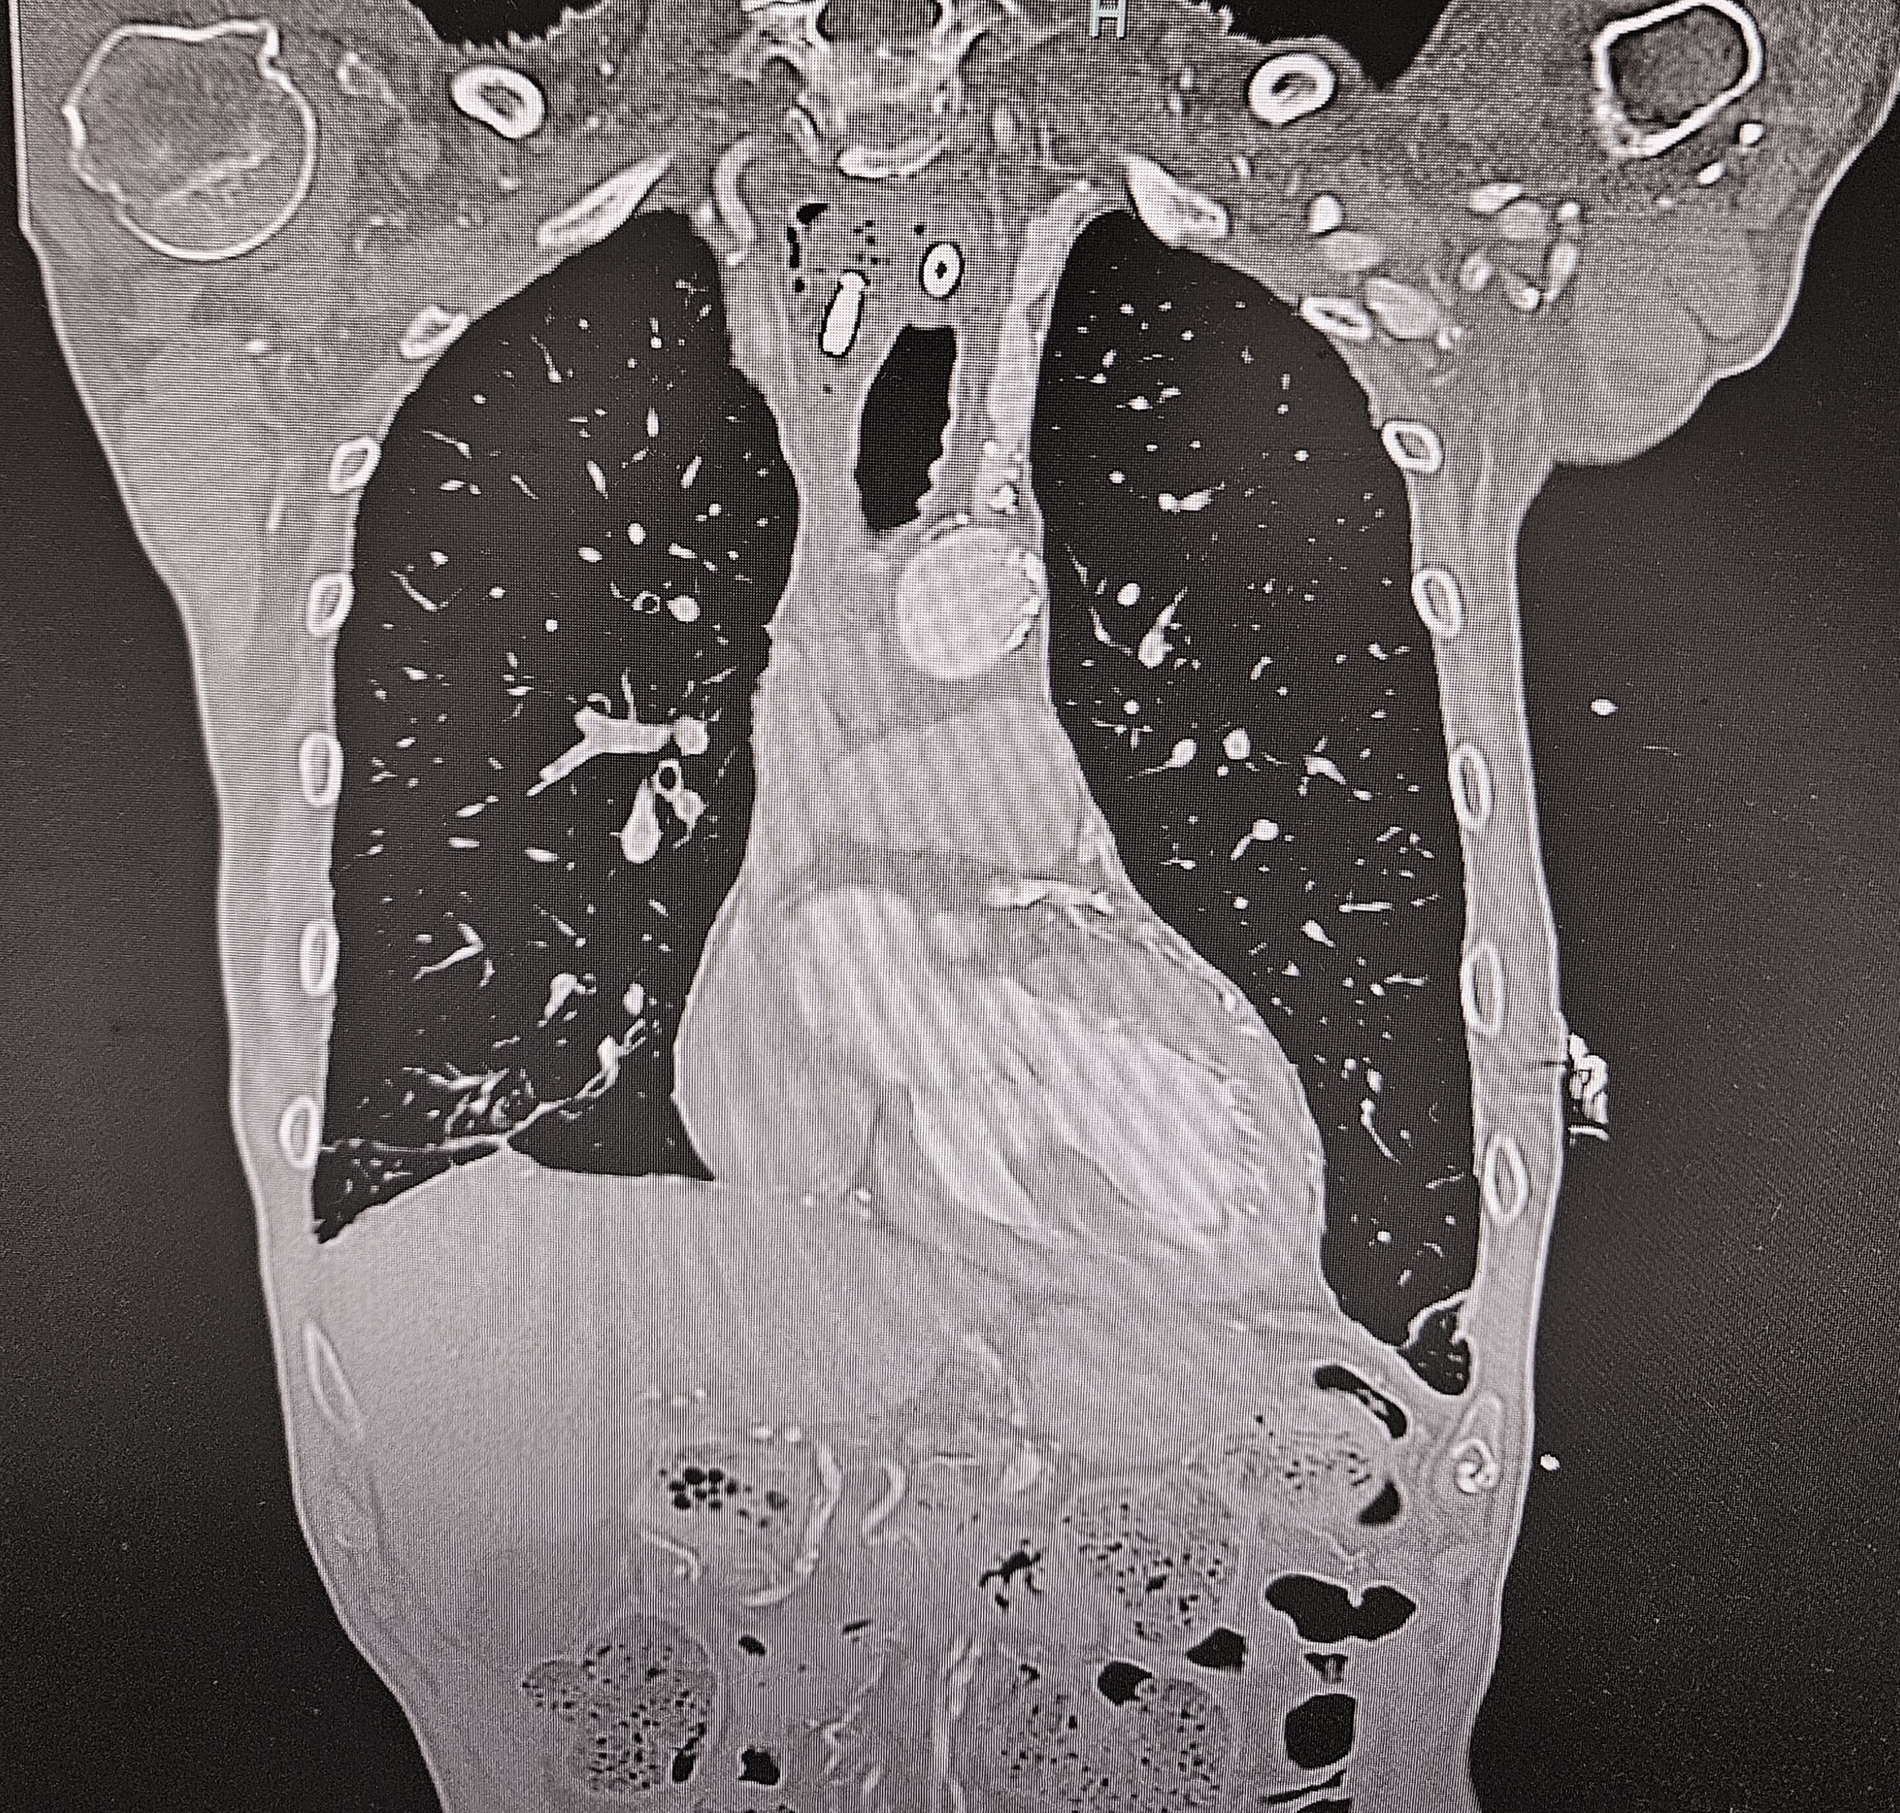

Während der Ösophagoskopie kam es zu einer traumatischen Perforation der Speiseröhre bei etwa 22 cm ab Zahnreihe. Zudem wurde während der Untersuchung ein anscheinend stark gelockertes dentales Implantat unbemerkt entfernt und nach aboral disloziert, bis es durch die simultan entstandene Perforation des Ösophagus in das Mediastinum verlagert wurde. Da eine intraoperative Verletzung des Ösophagus nicht ausgeschlossen werden konnte, wurde unmittelbar postoperativ eine Computertomografie von Hals und Thorax veranlasst. Diese zeigte rechtsseitig paraösophageal abgrenzbare Luft im Mediastinum, beginnend vom Kieferwinkel bis kurz kranial des Aortenbogens (Abbildung 1) sowie einen metalldichten Fremdkörper im Bereich des oberen Mediastinums (Abbildungen 2 und 3).